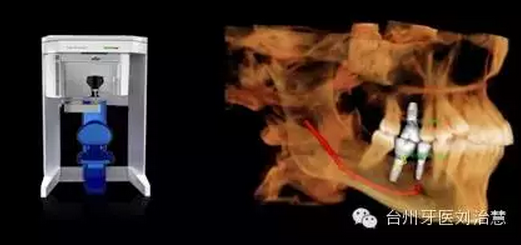

五、種植牙

145.png

種植牙的精確定位及術(shù)前輔助設(shè)計(jì)。華西口腔醫(yī)學(xué)院李娜、王虎等曾于2012年發(fā)表論文,旨在探討上頜竇生理及病理性CBCT 影像表現(xiàn),為上頜竇提升術(shù)解剖定位和操作入路提供參考依據(jù)。研究指出,CBCT 能夠準(zhǔn)確地顯示完整的上頜竇影像,利用 CBCT 確定解剖定位標(biāo)志,確定上頜竇提升手術(shù)路徑和方式,更符合安全、準(zhǔn)確、微創(chuàng)的口腔種植理念。該文發(fā)表于《中國(guó)口腔種植學(xué)雜志》2012年第3 期。

總之,CBCT數(shù)秒內(nèi)完成對(duì)患者的掃描,實(shí)現(xiàn)對(duì)種植位點(diǎn)的快速評(píng)估,并使用嵌入工具測(cè)量可以利用的骨量,發(fā)現(xiàn)隱藏的病灶。使用自動(dòng)神經(jīng)管標(biāo)記工具描繪出神經(jīng)管走行。直觀顯示骨內(nèi)阻生牙的精確位置,確定臨牙位置及毗鄰重要結(jié)構(gòu),包括神經(jīng)管、上頜竇壁和骨皮質(zhì)邊界。